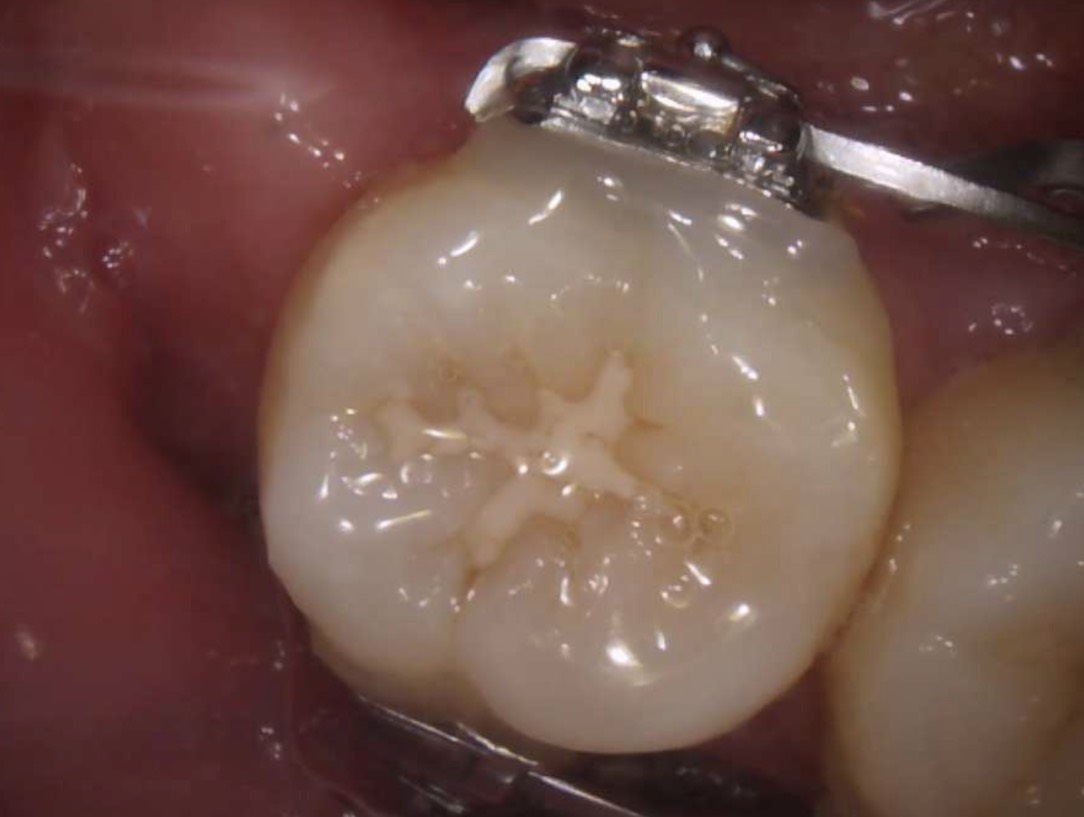

| 主訴 | 下の奥歯が黒くなっていて気になる |

|---|---|

| 所見 | 下顎右側第二大臼歯咬合面に充填物を認める。 |

| 診断 | 下顎右側第二大臼歯咬合面う蝕Ⅰ度 |

| 治療内容 | コンポジットレジン修復 |

| 治療後経過 | 痛みなく、咬合状態も良好。 |

| 治療期間 | 1回 |

| 治療費用 | 保険診療一本で1500円程度。 |

| リスク・副作用 | 今後も材料の経年劣化によって着色や不適合になる可能性があると伝えた。 |